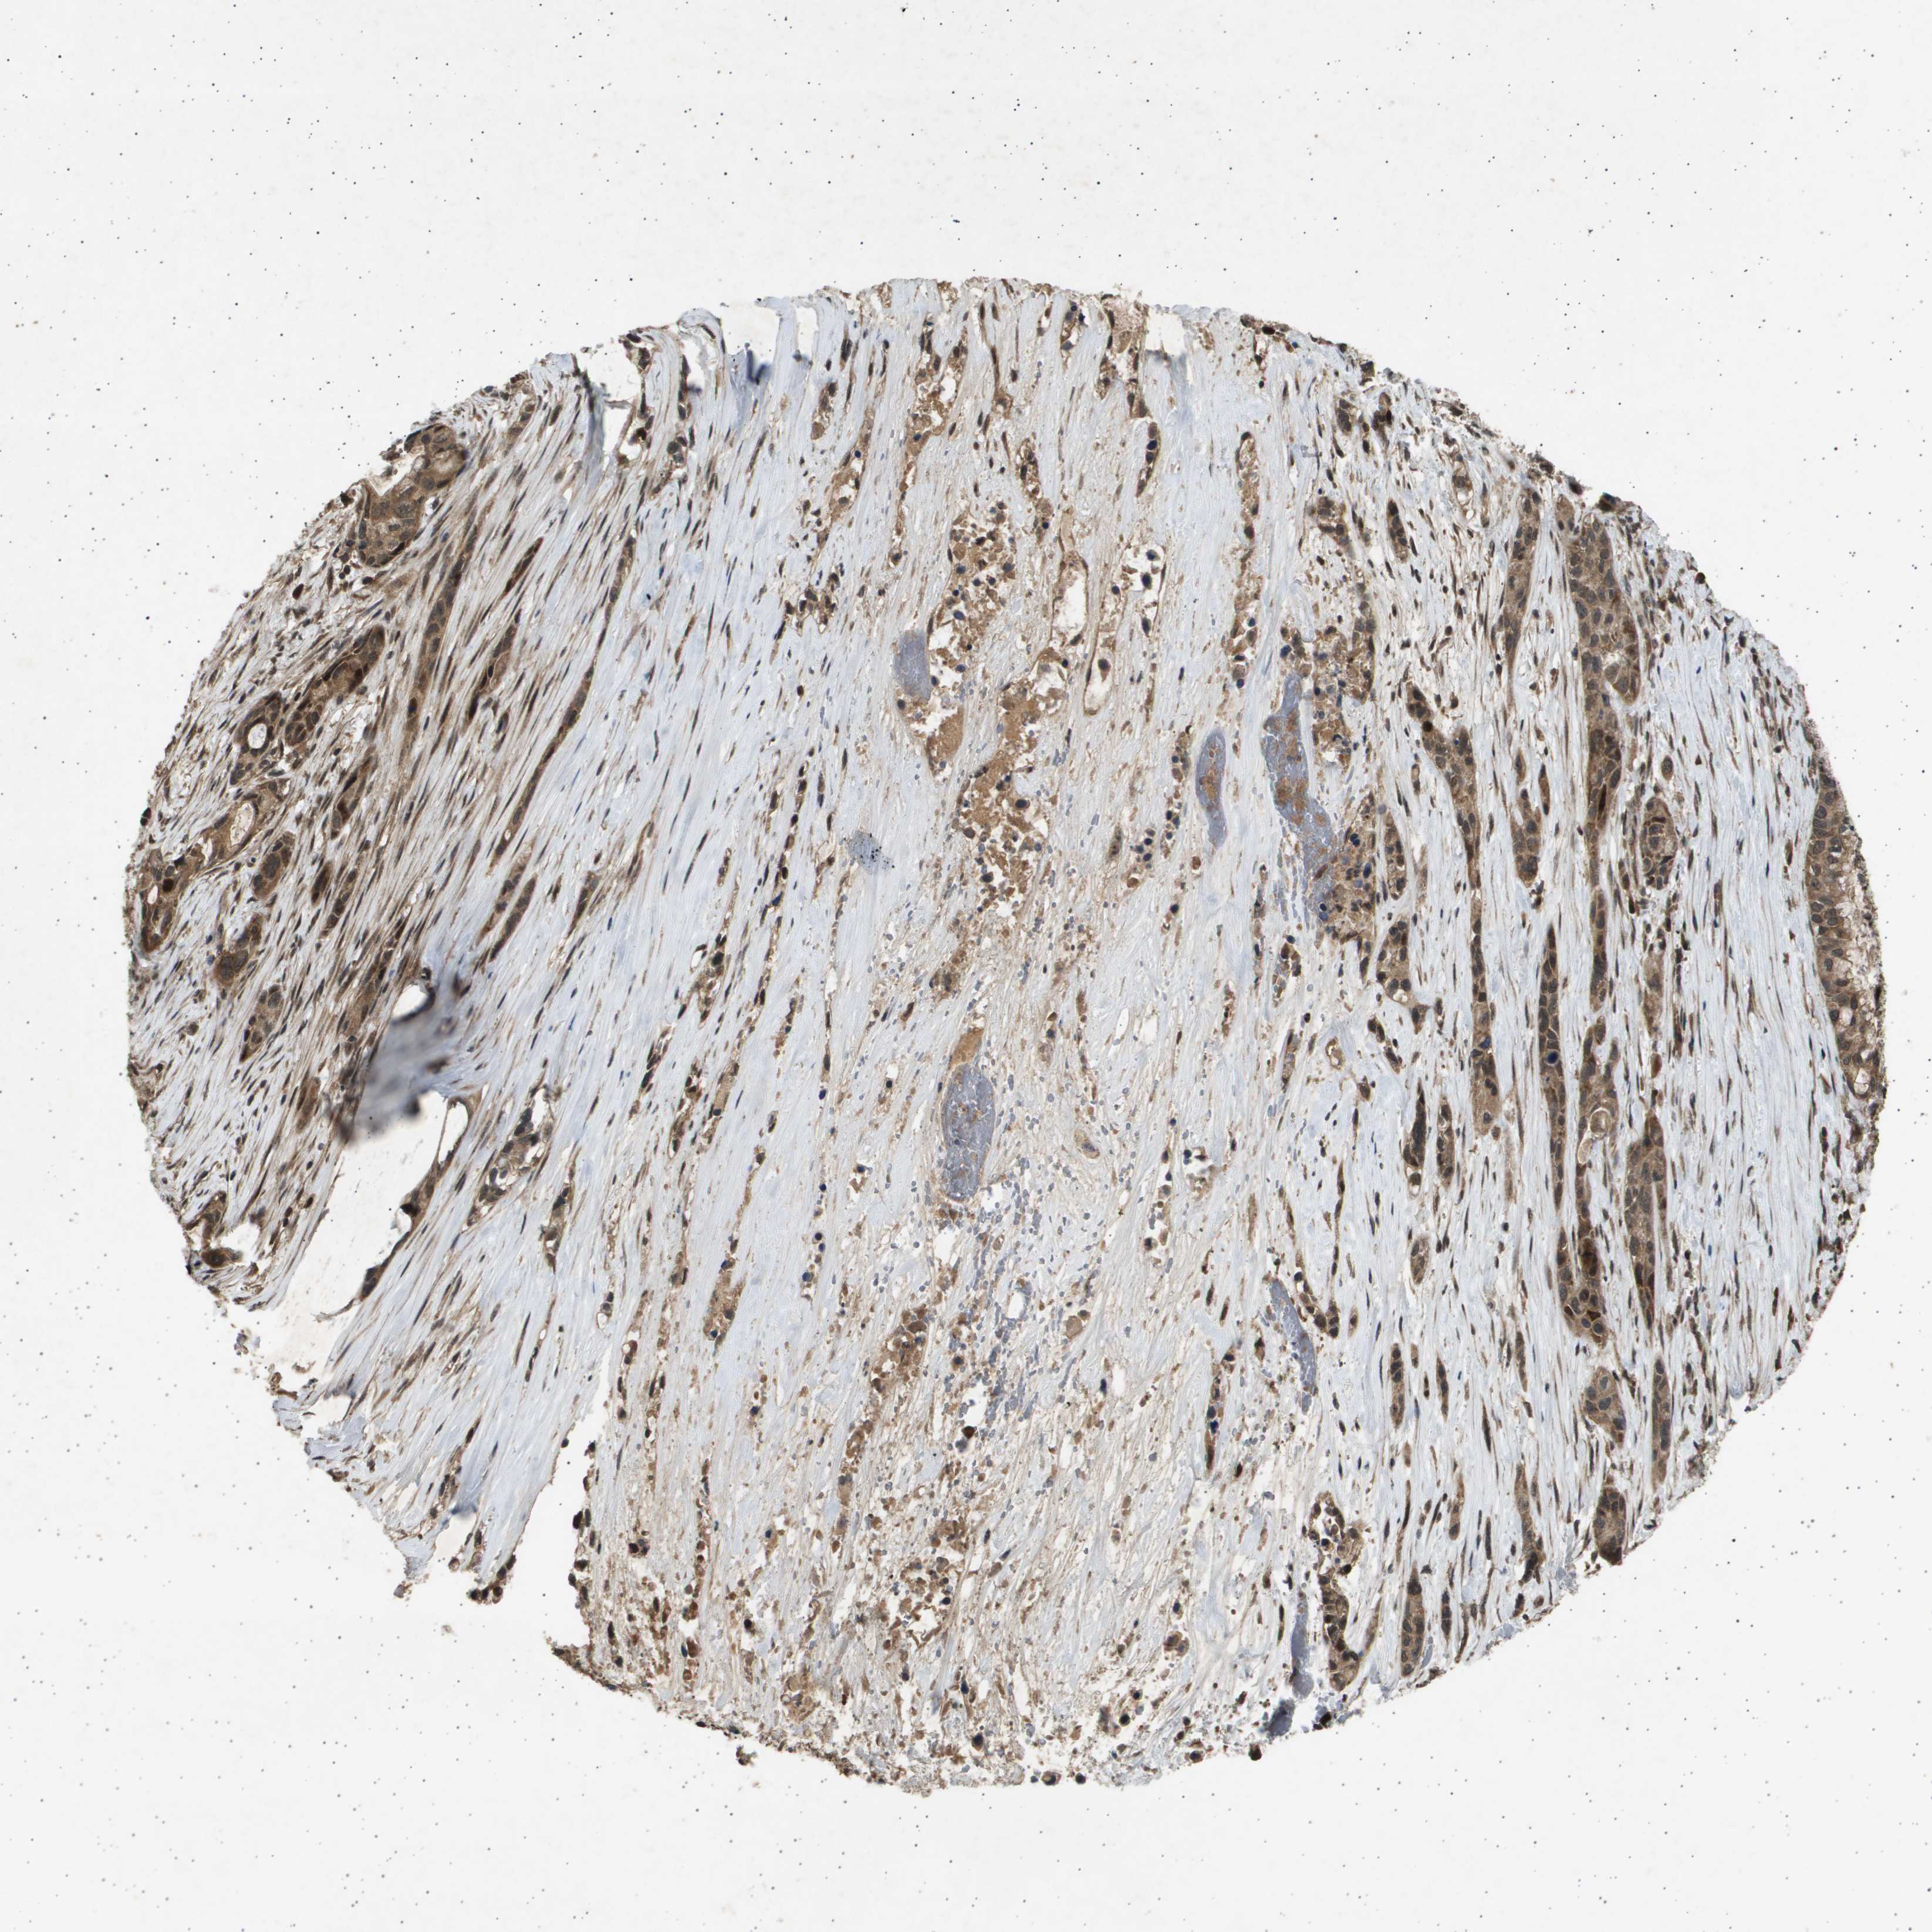

PANCREATIC CANCER - Protein expressioni

A mouse-over function shows sample information and annotation data. Click on an image to view it in a full screen mode. Samples can be filtered based on level of antibody staining by selecting one or several of the following categories: high, medium, low and not detected. The assay and annotation is described here.

Note that samples used for immunohistochemistry by the Human Protein Atlas do not correspond to samples in the TCGA dataset.

Antibody stainingi

Antibody staining in the annotated cell types in the current human tissue is reported as not detected, low, medium, or high, based on conventional immunohistochemistry profiling in selected tissues. This score is based on the combination of the staining intensity and fraction of stained cells.

Each image is clickable and will lead to virtual microscopy that enables deeper exploration of all samples and also displays staining intensity scores, fraction scores and subcellular localization as well as patient and tissue information for each sample.

Antibody HPA017869

Staining

High

Medium

Low

Not detected

Intensity

Strong

Moderate

Weak

Negative

Quantity

>75%

75%-25%

<25%

None

Location

Nuclear

Cytoplasmic/membranous

Cytoplasmic/membranous,nuclear

Adenocarcinoma, NOS